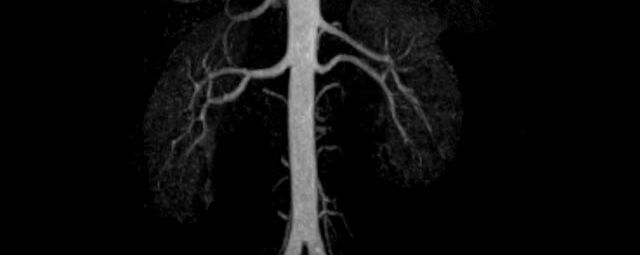

- Bauchgefäße

- Erfassung und Verlaufskontrolle bei arteriellen Aneurysmen (Aussackungen der Arterien), vor allem der Bauchaorta

- Darstellung von Gefäßengen an Nierenarterien, Baucharterien und Becken-/Beinarterien

- MR-Angiografie ohne Kontrastmittel

- Time of Flight (TOF)-Angiographie

- Phasenkontrastangiographie (PCA). Geeignet zur Quantifizierung Stenose-/Insuffizienzgrad z.B. bei Herzklappen, falls echokardiographisch die Untersuchungsbedingungen eingeschränkt sind.

Je nach Fragestellung und Körperregion Gefäßdarstellung ohne Kontrastmittel bei Kontrastmittelunverträglichkeit oder terminaler Niereninsuffizienz möglich.

- MR-Angiographie mit Kontrastmittel

- Erfassung arterieller und venöser Gefäße/Bypässe aller Körperregionen mit 3D-Rekonstruktion

- je nach klinischer Fragestellung zeitaufgelöste MR-Angiographie (4D-MRA) z.B. bei Frage arteriovenöse Fistel/ Shunt oder Darstellung Unterschenkelarterien vor geplanter Bypassoperation.